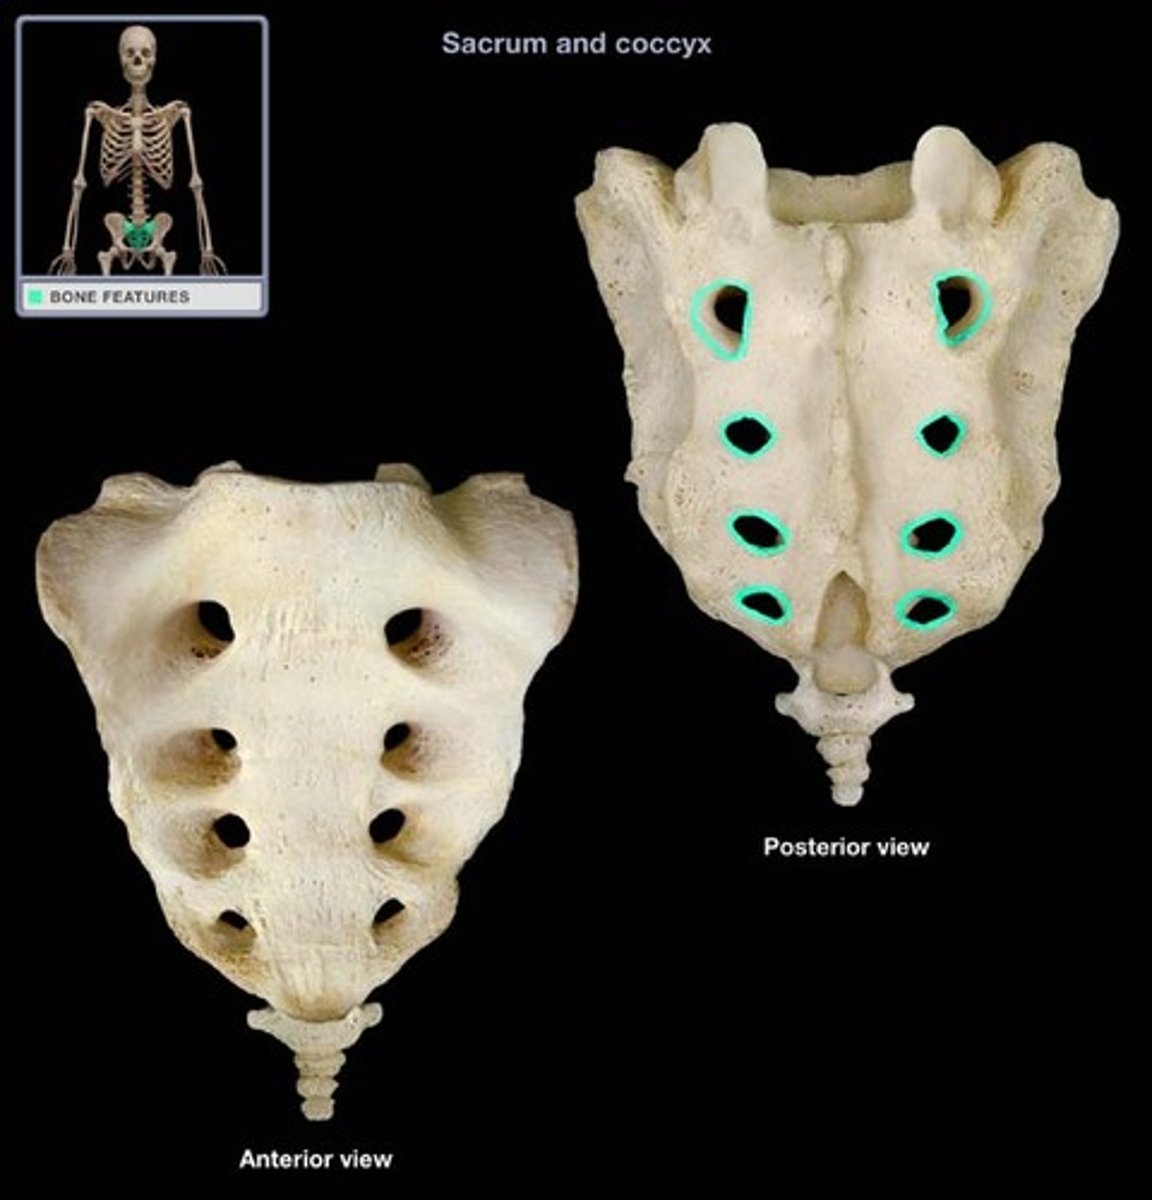

Sacral canal

Sacral hiatus

Sacral foramen/foramina

Median sacral crest